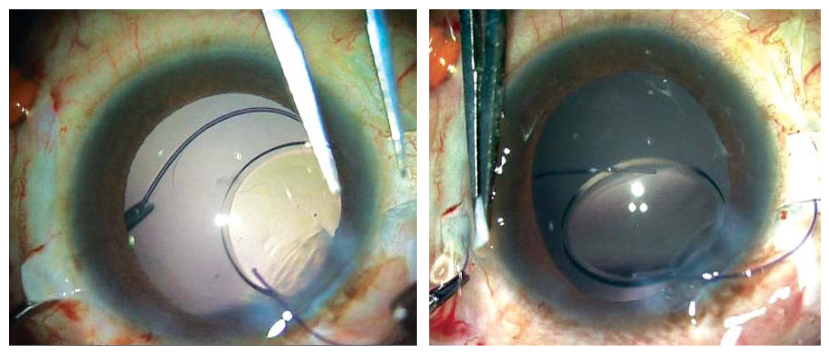

图4A至C:A,术前裂隙灯照相显示IOL脱位至前房内;B,术后第一天;C,术后三个月。